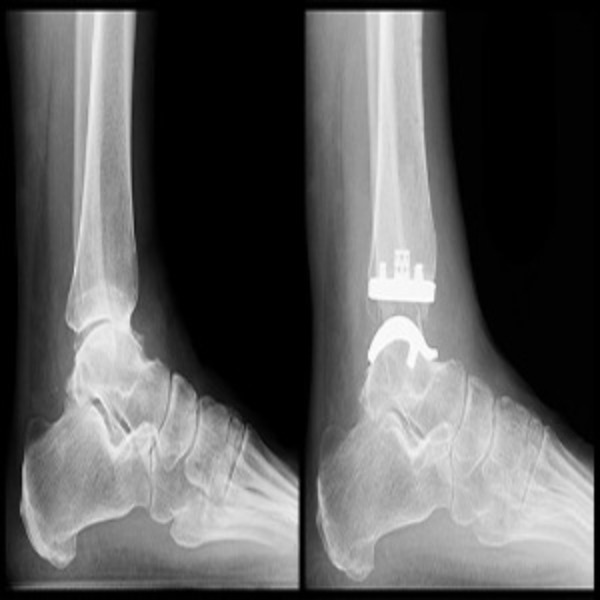

Suyog Hospital Nagpur - We Provide Best Doctor For Ankle Replacement Surgery